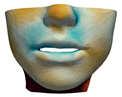

2.6. Textured Output Visualization